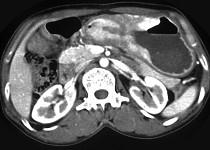

问题 女,56岁,上腹部钝痛、腹胀不适1月余,纳差、消瘦,影像检查如图,最可能的诊断是 ( )

选项 A.胃幽门管溃疡 B.胃腺癌并幽门狭窄 C.胃淋巴瘤 D.胃间质瘤 E.胃恶性间质瘤

答案 B